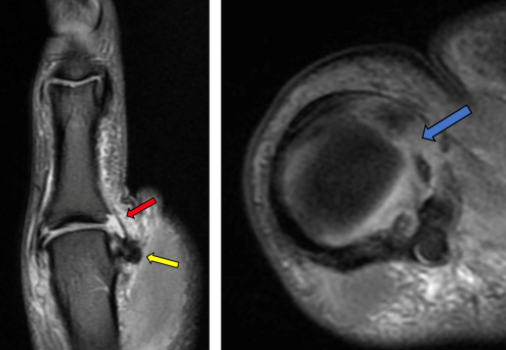

MRI상 화살표 부위의 인대 결손부위 및 근위부로 덩어리처럼 관찰되는 병변